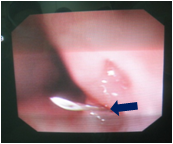

吻合口狭窄

气管软化

食道气道瘘复发